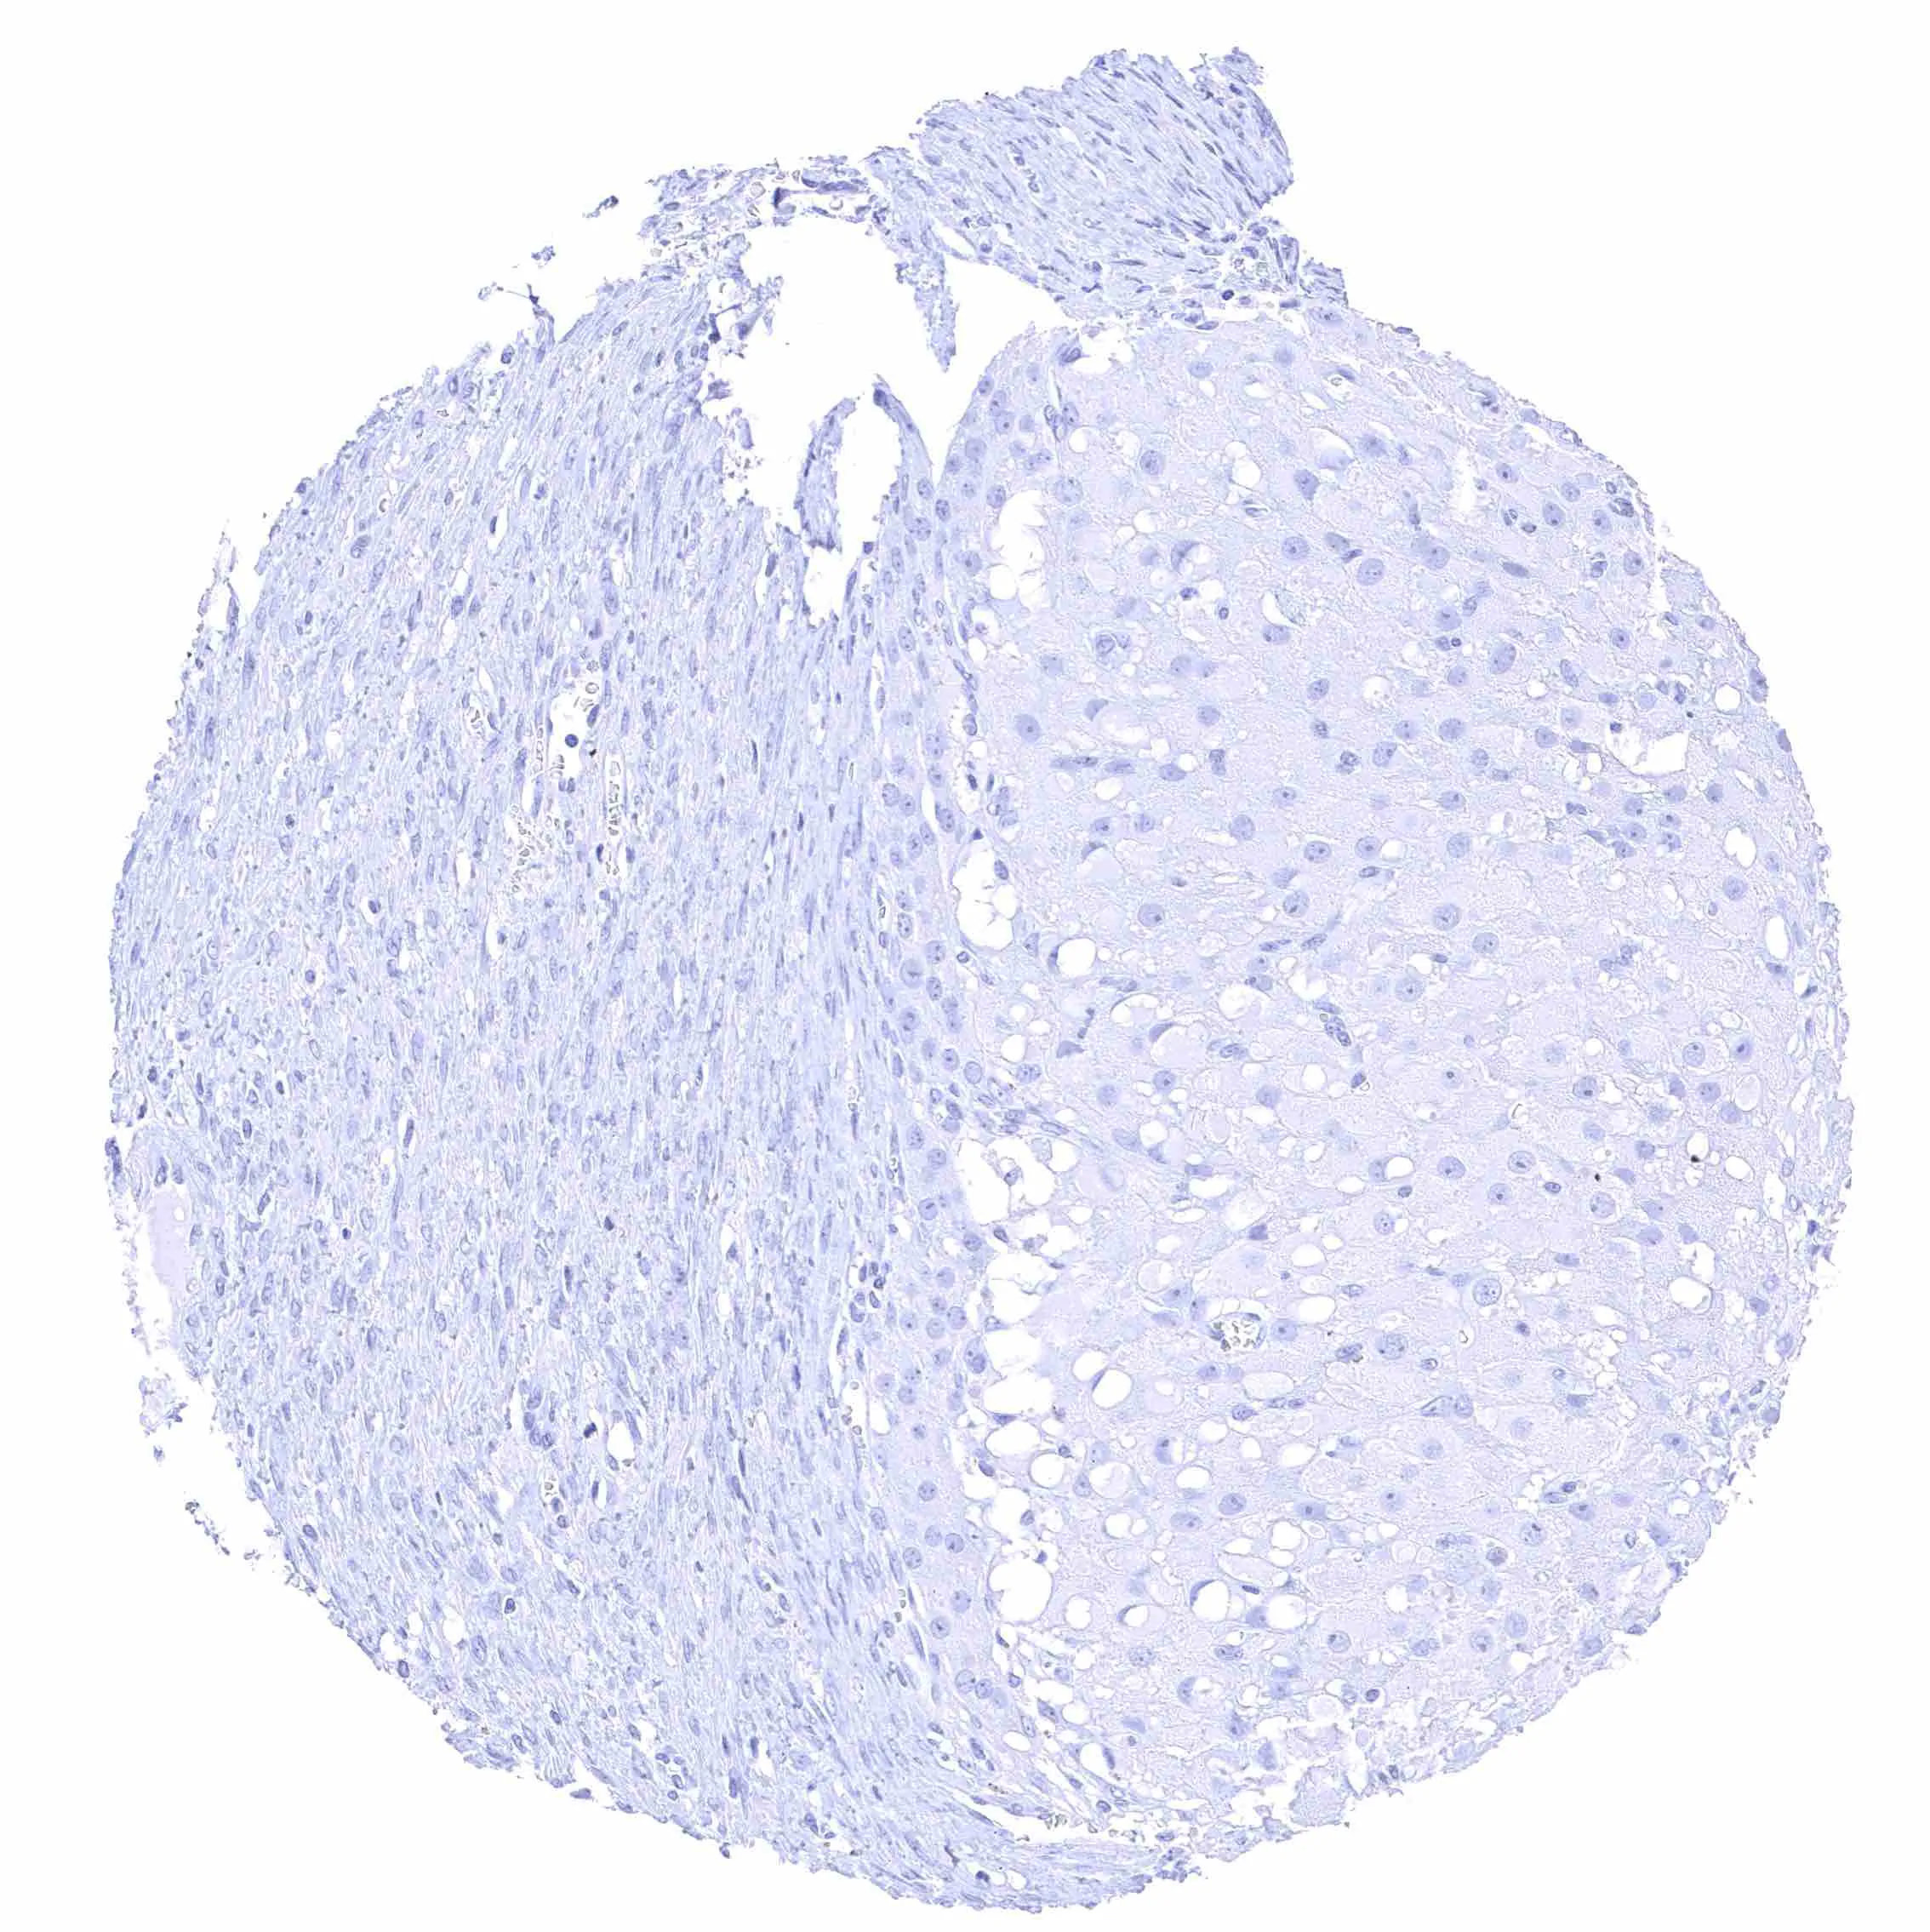

Liver